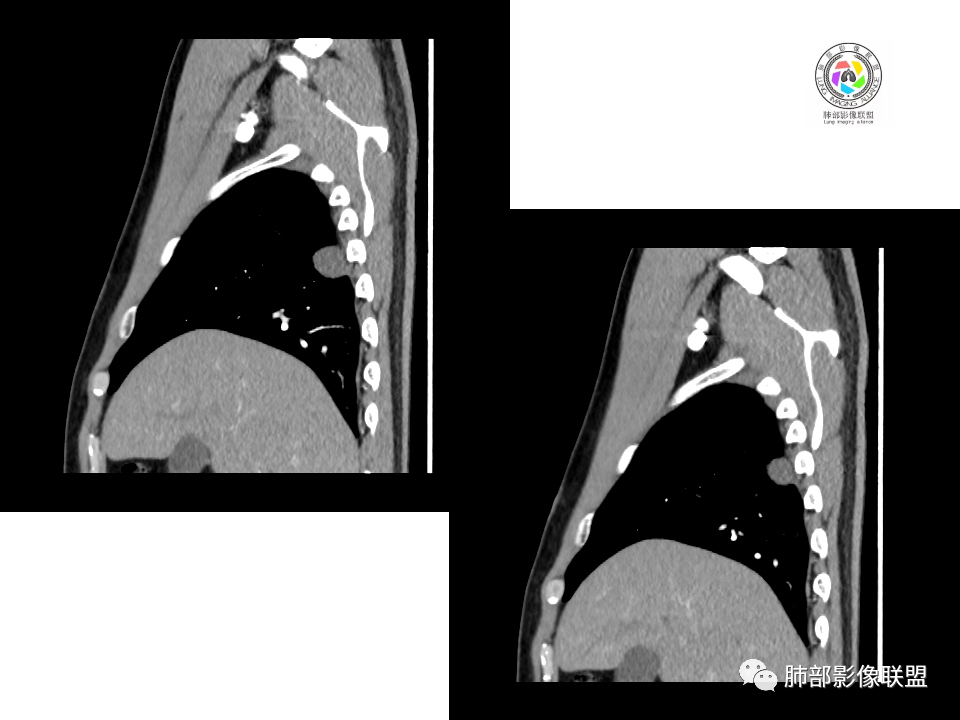

2.右肺下叶背段胸膜下块影,边界清楚光整,上下极见磨玻璃晕,未见明显分叶毛刺和棘状突起,未见胸膜凹陷或胸壁侵入。密度均匀,轻度不均匀强化。未见支气管进入。

4.右肺下叶基底段支气管血管束旁小结节影,边界清楚,强化不明显。注意,这结节在“遥远的”基底段。

显然本例焦点在于背段那个边缘光整的块影!

右肺下叶占位,胸膜下,与胸膜关系密切;

密度均匀;糊墙,边缘膨隆为主;

部分血管推移。

支气管如何?